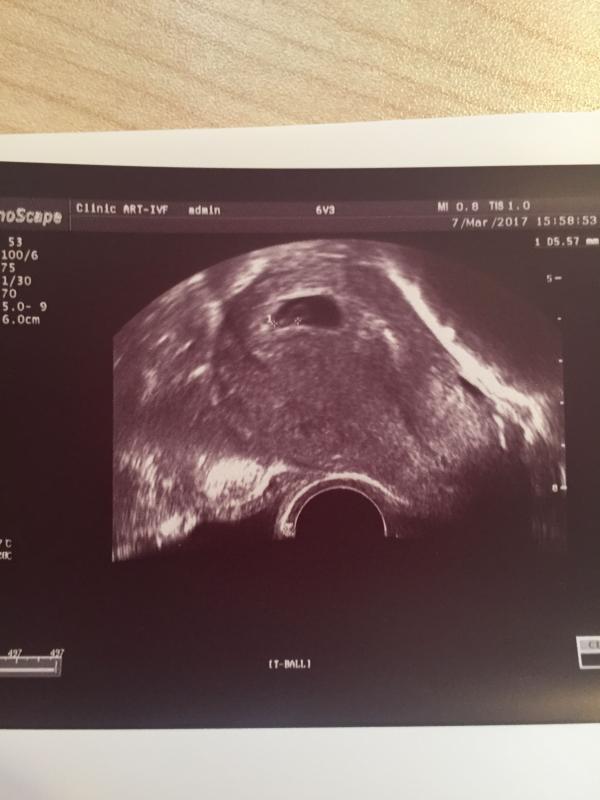

Ура, впервые увидела СБ! Нам сегодня 6н и 3д. Спасибо большое Веряевой Надежде Александровне из "Арт-Эко" за тернистый путь к нашему счастью💐! Девочки, подскажите, гинеколог-репродуктолог ведёт до 12 недели, потом передают акушерам, кто-нибудь вёл беременность в Арт-Эко и у какого врача? 😊